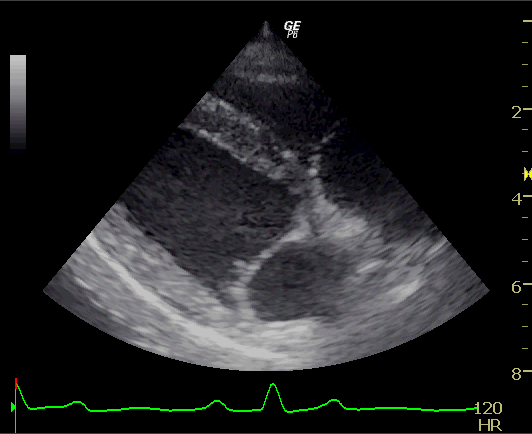

②心臓超音波検査

心臓の機能的評価を行います。

心臓内部の弁の逆流や狭窄が生じていないかどうかを確認し、同時に心房心室の拡大や心筋壁の肥大を評価します。

また、猫では血栓がないかどうかを見ています。

正常な犬

心臓病(僧帽弁閉鎖不全症)の犬

僧帽弁閉鎖不全症の犬では僧帽弁が厚くなり、きちんと弁がしまっていません。